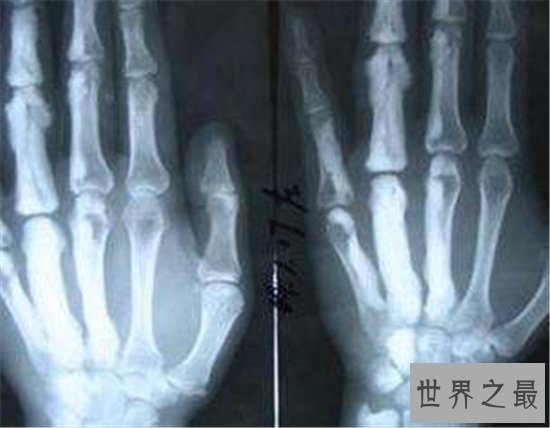

4、骨肉瘤

骨肉瘤是多发于年轻人群中的一种病症,主要表现在骨关节中增生的小肉瘤。而这个病症的诱因,重点就是我们对手机电脑等电子产品的长期使用,过度劳损手臂与肩膀等常用关节的后果显然是不容小觑的。万幸骨肉瘤在今天还是比较容易治愈,对人体健康的威胁也并不算大。